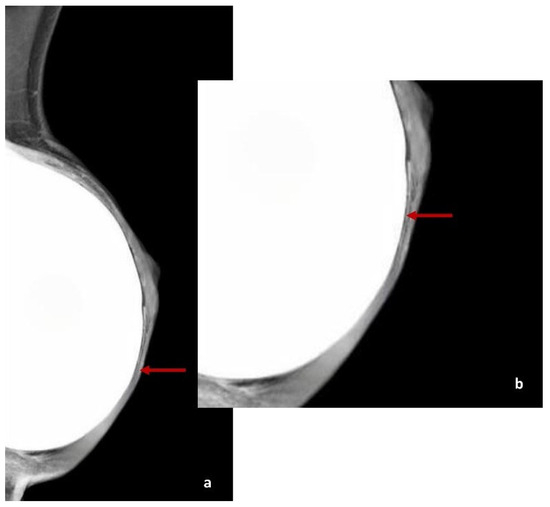

4.1. DM Features of ADM

| DM | Derived from pig dermis | Two patients (3%) | One patient (2%) | Zero patients (0%) | Radiological signs visible on DM completely disappear at T2 |